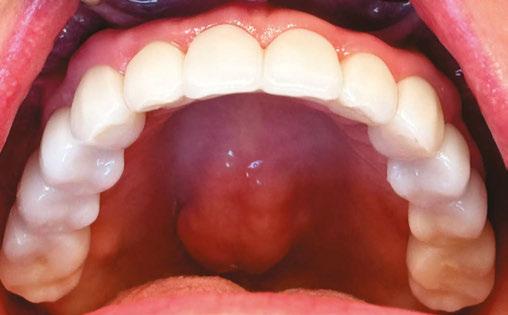

The concept behind the 3 on 6™ is elegantly simple and biomechanically sound: six dental implants are placed to support one solid arch of teeth, providing cross-arch stabilization. After allowing time for osseointegration, the single arch is replaced with three segmented zirconia bridges — one on the anterior and one on each posterior quadrant. No bone removal necessary. No artificial gum material. No bulky prosthetics. Just permanent, implant-supported teeth that feel and function more like the real thing.

This segmentation turned out to be a game-changer. Unlike a monolithic denture-like restoration, segmented bridges allowed for healthier force distribution, improved hygiene, and superior phonetics. Patients retained their natural bone architecture, which allowed for better esthetics and long-term oral health. Because the bridges sat directly over the ridge rather than floating over pink acrylic, food impaction was minimized — and when it did occur, cleaning was far more manageable. There were also nearly no cases of prosthetic fractures with the final segmented zirconia bridges, and in cases where there were needs for replacement, it was much cheaper and easier to replace a 4-unit bridge than an entire full-arch fixed prosthetic.

Most importantly, patients loved the feel. The 3 on 6™ doesn’t rely on the palate for stability, doesn’t need to be removed for cleaning, and doesn’t simulate tissue — it replaces only the teeth. For patients who had struggled with dentures or the “false” feeling of All-on-4, this was a restoration that felt like they had their real teeth back.

tists would use the term “unicorns” when describing how rare they felt it was for a patient to qualify for FP1 treatment. Over 10 years of 3 on 6™ treatment has proven that is not the case. Today, Dr Roberts believes the vast majority of patients in need of full arch teeth restoration qualify for FP1 or FP2 treatment. Many patients have even converted from All-on-4 prosthetics that they hated to more natural feeling 3 on 6™ bridges that they love.

Today, the 3 on 6 is being performed in clinics across the U.S. and Canada by trained and licensed providers. Thousands of patients each year are receiving permanent smile restorations that are more affordable, more hygienic, and more natural-feeling than traditional options. Patients love that their teeth never have to be removed. They love that there is no transition line beneath their gums, and they love how it feels inside their mouth. In a street survey where patients were shown side-by-side retracted photos of All-on-4 and 3 on 6 smiles, 98% of respondents said they felt the 3 on 6 looked better and more natural.